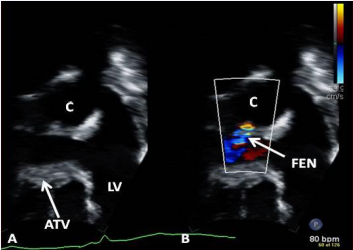

Stage IIIB: During the Stage IIIB, the fenestration is occluded (Figures 35) by transcatheter methods [32,46,82,85-87], usually 6 to 12 months following Stage IIIA Fontan. In the past, most devices used to occlude ASDs [46,87-87], were used for this purpose, but now, Amplatzer Septal Occluders are the most frequently used devices to accomplish such closures. If there are any other residual shunts, they are also occluded by device closure.

Figure 32 Selected video frames (A and B) from an apical four chamber view focusing on the conduit (C) (A) and with color flow imaging (B) demonstrating fenestration (FEN). ATV, atretic tricuspid valve; LV, left ventricle [69].

Figure 32: Selected video frames (A and B) from an apical four chamber view focusing on the conduit (C) (A) and with color flow imaging (B) demonstrating fenestration (FEN). ATV, atretic tricuspid valve; LV, left ventricle [69].

Figure 33 Selected video frame with Doppler sampling across the fenestration (Fen) demonstrating a mean gradient of 8 mmHg [69].

Figure 33: Selected video frame with Doppler sampling across the fenestration (Fen) demonstrating a mean gradient of 8 mmHg [69].

Echocardiographic and angiographic examples of the Fontan procedure are shown in Figures 29 to 34.